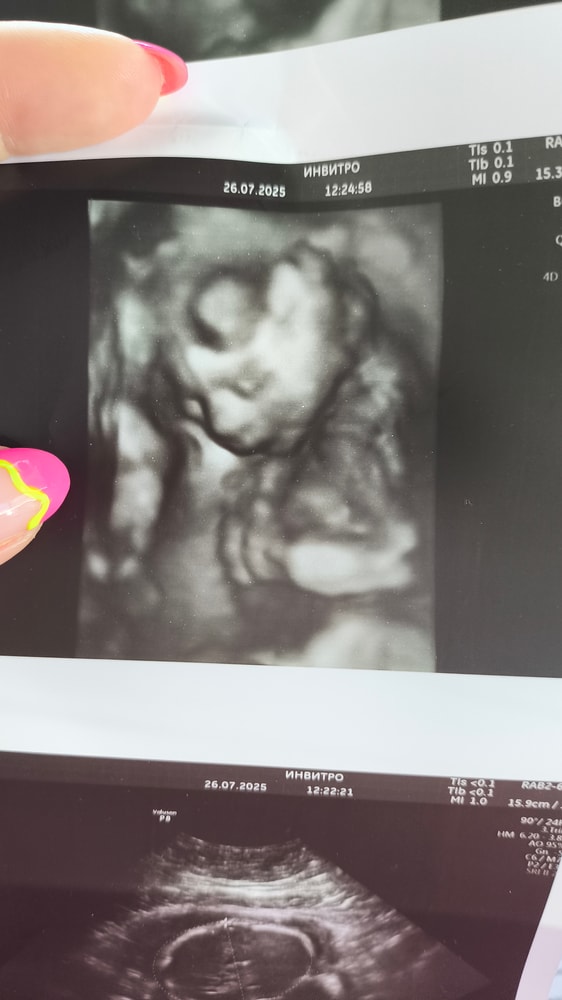

Изображение В нашем случае и до 25 уже можно понять на кого похож)

Олеся, Изображение

Олеся, сладкая булочка! Тьфу тьфу тьфу! Большое спасибо за фото 🙏🏼

Была вчера, ровно 25 было, хорошо видно, только может не показаться или закрыться руками 😅 ходила гулять на второй раз успели заснять без рук 😂

Сходила на УЗИ 3D/4D УЗИ в 25 недель